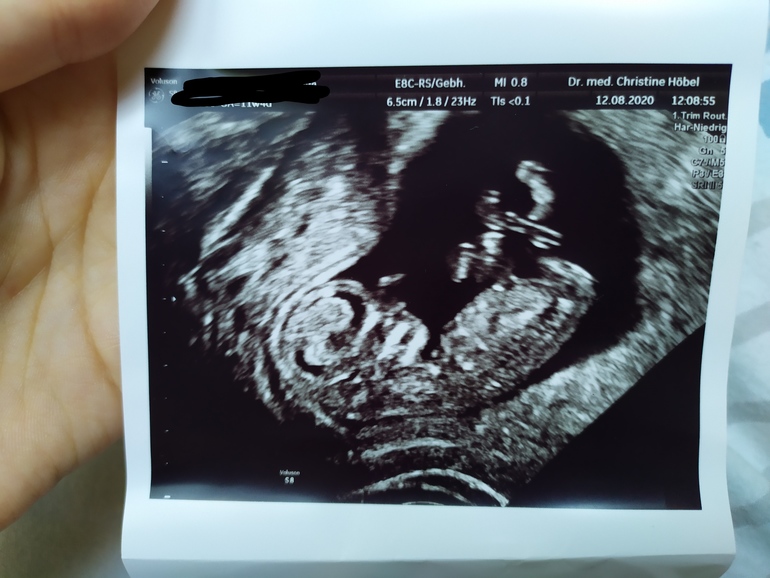

Первый скрининг - done✔️

Пол малышаДобрый день ББ)) сегодня я прошла свой первый скрининг,слава Богу вроде всё в порядке, ТТТ! Тут конечно такой скрининг, НЕДОскрининг... Срок 11+4.

Вопрос к вам девочки, кто что скажет по поводу пола малыша? Мне кажется на этих фото половой бугорок не попал "в кадр", но может вдруг кто разглядит🤪 в Германии пол до 14 недель не говорят😔 для меня это в общем-то не особо важно, хотелось бы девочку конечно, но если мальчик тоже не расстроюсь. Вроде🤭 муж зато наоборот хочет пацана. Ну короч стандартная ситуация 🤦😆 мне главное чтоб ребёнок здоровый родился и желательно под счастливой звездой как говорится 🙈😄

Малышок сначала походу дрых, а потом как забацал сальто и перевернулся на другую сторону)) так мило))) думала буду реветь, неее, лежала как мумия в монитор таращилась с покер фэйс😆 а вот когда уже фото дома начала рассматривать так сидела лыбилась как дура🥴😄😍